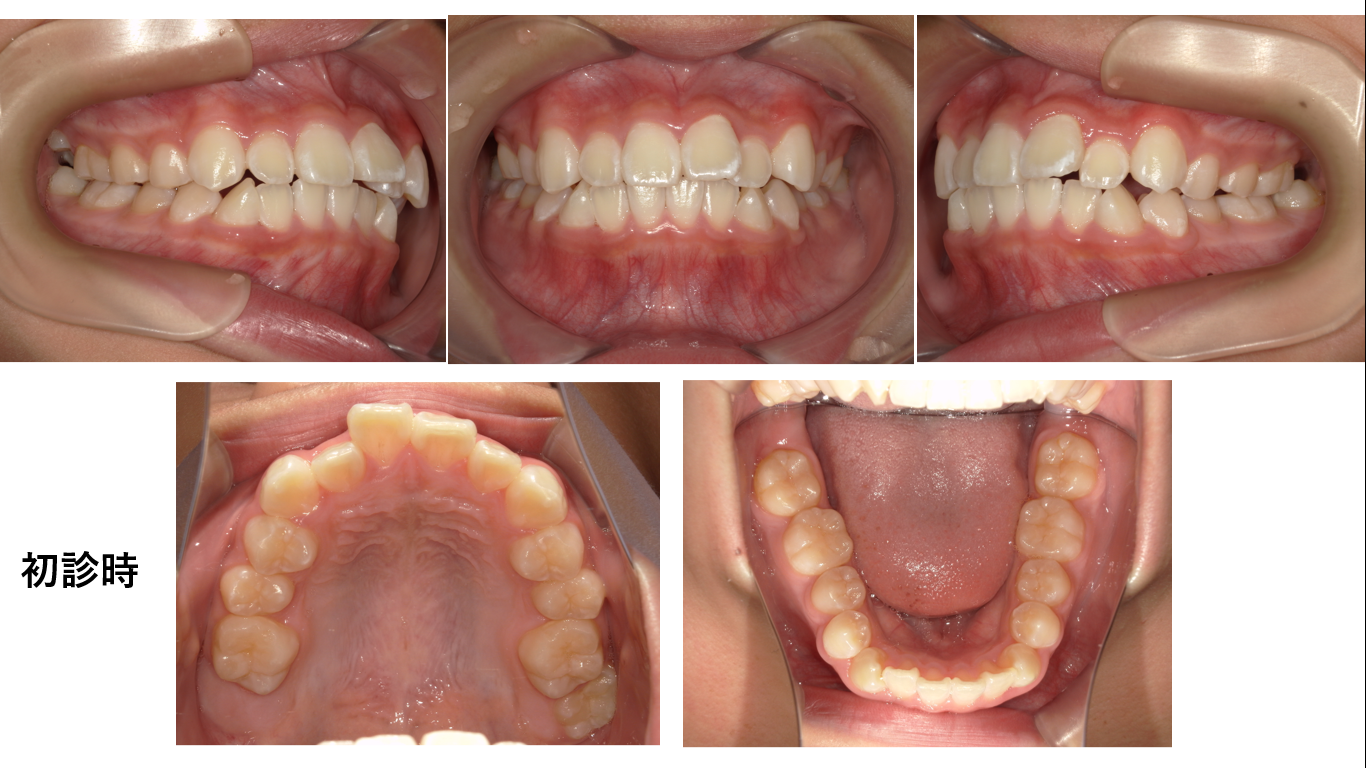

矯正症例148 AngleⅠ級上顎前突、裏側矯正、舌側矯正

初診時12歳、抜歯部位:上顎左右4番、8番、下顎左右4番、治療期間2年6か月、治療費総額146万円(税込み)歯列矯正には以下のリスクを伴う場合があります。1最初は矯正装置による不快感、痛み等があります...